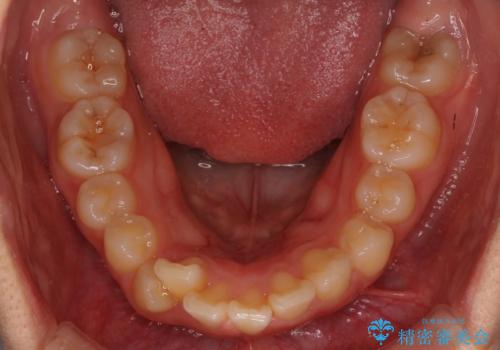

- 矯正装置

- 審美装置

上下左右の小臼歯を抜歯しています。